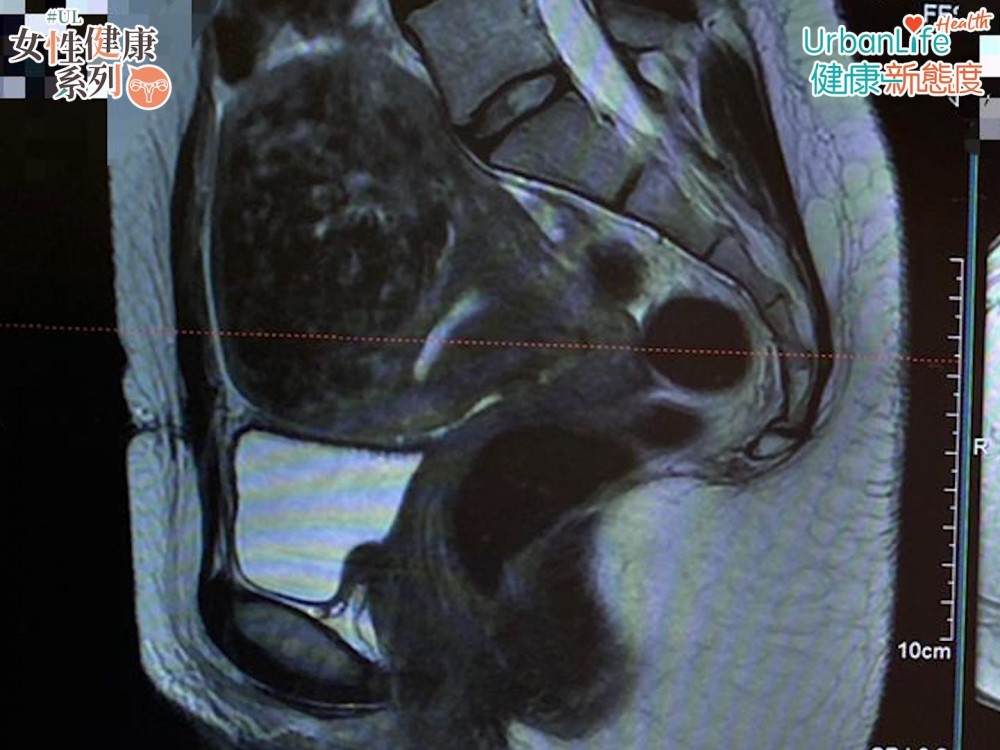

今年36歲的全職媽媽周小姐,一向都有定期做婦科檢查的習慣。在上年5月照超聲波時,發現自己子宮內,有一粒8至9CM的良性肌瘤,屬漿膜下肌瘤。她指,發現患病時,心情都頗為愕然,同時亦擔心肌瘤會否影響其肚內的小朋友,又或會令她不能懷孕。

1-漿膜下肌瘤

肌瘤於子宮外圍出現,如肌瘤的體積較大,或會令患者出現「頂胃」的情況。